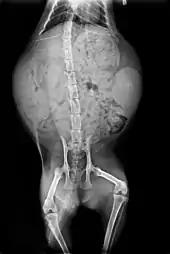

Anatomie des organes vitaux du chat.

L'anatomie du chat est semblable à celle des autres espèces de félidés. Il possède un corps fort et flexible, des réflexes rapides, des dents pointues et des griffes rétractables adaptées à la mise à mort de petites proies.

Le squelette est composé de 250 os. Les vertèbres du cou sont courtes, et la colonne vertébrale est très souple.

La clavicule des chats, de petite taille comme pour tous les félins, est reliée au sternum par un unique ligament : cela lui confère une grande souplesse, les épaules pouvant bouger indépendamment l’une de l’autre. Comme tous les carnivores, la dernière prémolaire supérieure et la première molaire inférieure forment les carnassières qui permettent au chat de déchirer sa nourriture, grâce à des muscles puissants fixés aux parois latérales de son crâne, et de l’avaler sans la mâcher. L’os hyoïde est entièrement ossifié, ce qui permet au chat de ronronner mais pas de rugir[14].

Les pattes sont pourvues de griffes rétractiles. Le chat possède cinq doigts aux pattes antérieures, dont seulement quatre touchent le sol, le pouce restant à l’écart, ainsi que quatre doigts aux pattes postérieures[14]. Des cas de polydactylie existent et certains standards de races de chats l’admettent dans les concours[A 3]. Les coussinets ou pelotes, sont constitués d’une membrane élastique qui confère une marche silencieuse[15].

Vue externe et squelette du chat.